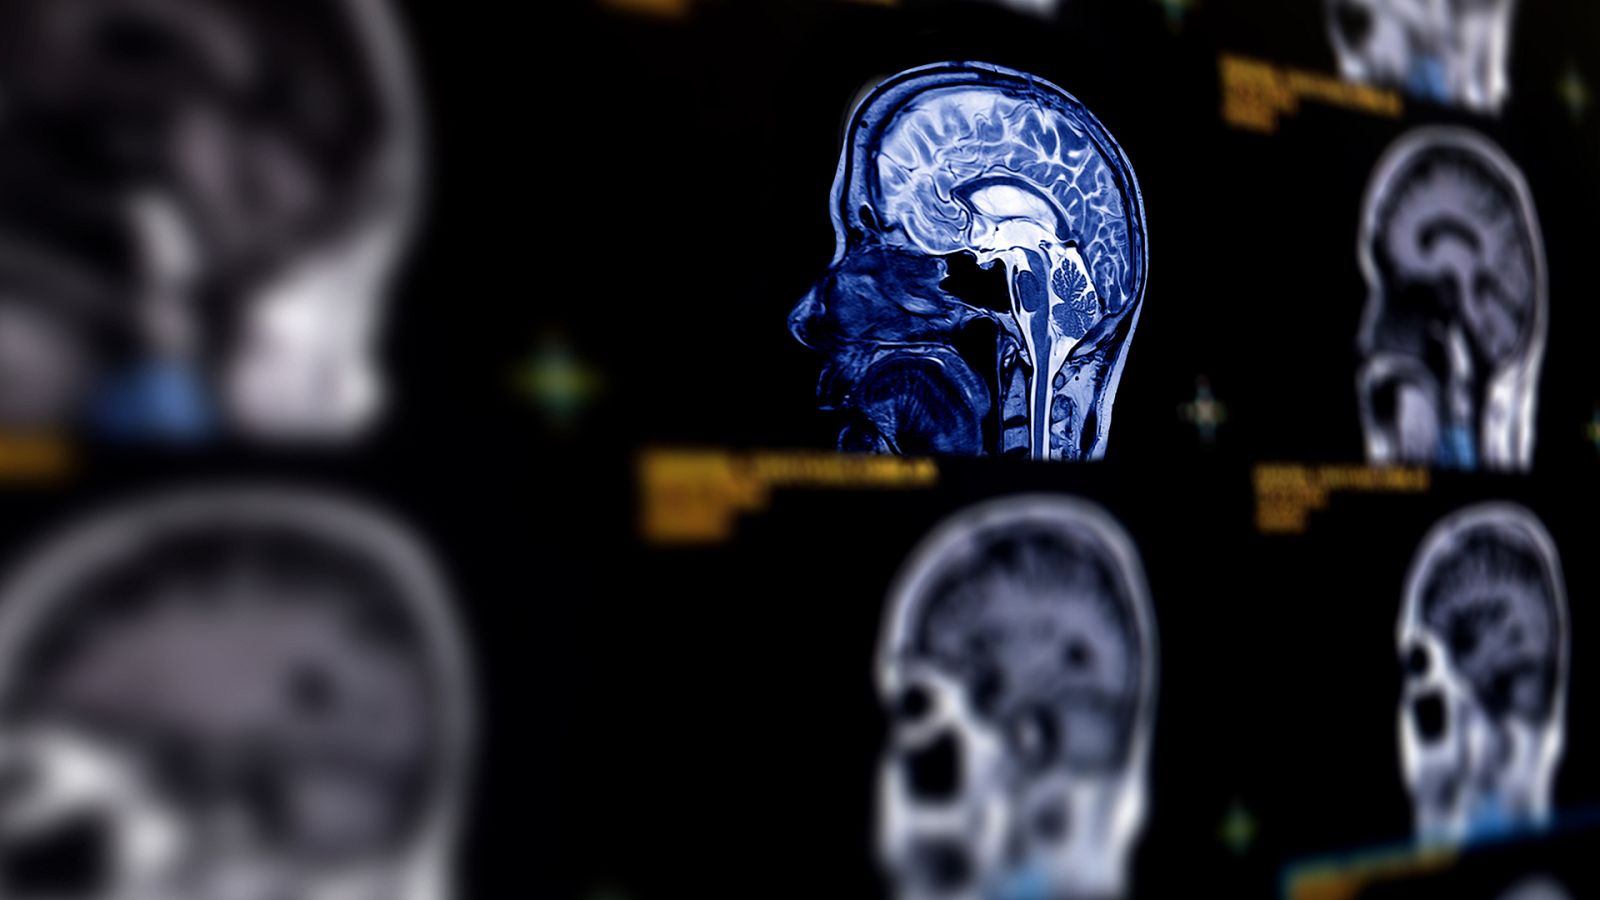

El ictus isquémico, que representa el 85% de todas las embolias, se produce por la obstrucción de un vaso sanguíneo cerebral y provoca 6 millones de muertes cada año en el mundo, siendo la segunda causa de fallecimiento. Si no mata, el ictus puede dejar importantes secuelas de por vida -de hecho es la primera causa médica de discapacidad en el mundo-, incluso en aquellos pacientes a los que, de forma mecánica, se les logra extraer el trombo de la sangre.

En las primeras 24 horas de la aparición del ictus, el tratamiento se basa en la administración de un fármaco endovenoso, la alteplasa; y practicar una trombectomía mecánica, que consiste en introducir un catéter por la arteria hasta llegar al trombo, con el fin de extraerlo. En el 85% de los casos se logra retirar el trombo y restablecer la circulación de la sangre en el cerebro, pero esto no es siempre una garantía de total recuperación, pues a los tres meses son muchos los pacientes que presentan secuelas o algún tipo de discapacidad.